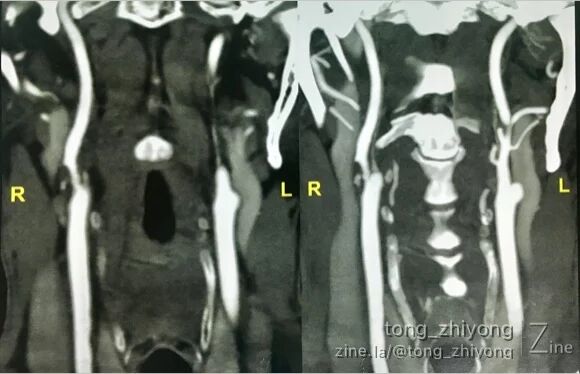

CTA可见:右侧颈动脉重度狭窄,动脉粥样硬化斑块破裂,造影剂进入斑块。

术后一周CTA可见:颈动脉通畅,颈内动脉起始部管径适度增宽。